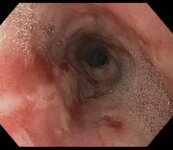

Large gastric ulcer along the lesser curvature with a visible vessel in the ulcer bed (arrow)

From the collection of Douglas G. Adler, MD